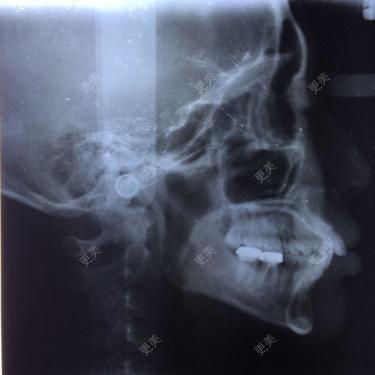

请问我这种程度矫正,需要拔牙嘛,因为觉得自己侧面最突,而且下巴有点后缩,牙齿矫正后这两方面会改善嘛单纯牙齿矫正可能不能解决问题。需要将牙槽骨后退。就是做上下颌骨后退手术。

• 单纯牙齿矫正可能不能解决问题。需要将牙槽骨后退。就是做上下颌骨后退手术。